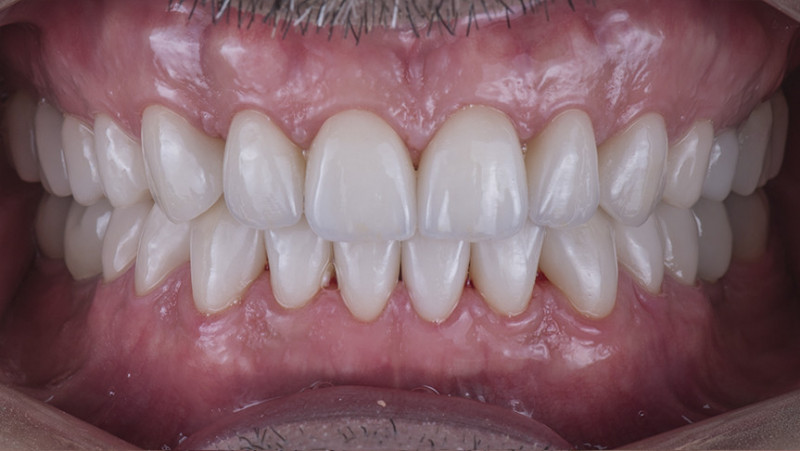

Установка керамической коронки

Изготовили и установили 22 керамические коронки EMAX и 6 виниров на нижнюю челюсть. Провели пластику десны в области 22 зуба. Устранили сильную рецессию десны в области имплантата, установленного в другой клинике.